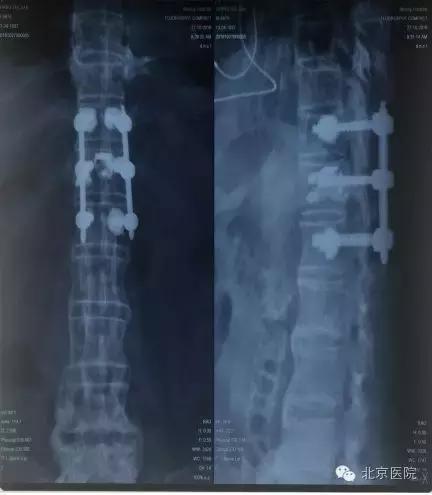

近日,北京医院骨科成功应用新型经皮骨水泥螺钉强化系统,微创治疗高龄合并多种复杂内科疾病的强直性脊柱炎脊柱骨折患者,这也是国内该领域的首例成功病例。

在医院的支持鼓励下,邀请在骨科麻醉方面具丰富经验的麻醉科专家周炬主任医师对患者进行了全身麻醉。在手术室王晓、程晓东、季洁等同事的的紧密配合下,孙常太副主任带领张良、张啟维副主任医师,成功为患者施行了经皮微创骨水泥螺钉强化固定术。手术中先经皮施行椎弓根螺钉固定,然后利用螺钉侧孔注入骨水泥进行强化。手术过程非常顺利,手术时间约2小时、手术中未输血,未放置引流管,术后第2天,患者即感术前症状明显改善。术后第5天即可坐起并活动,恢复了独立行走及站立的功能,术前疼痛完全消失。术后患者很快出院。此次手术既实现了微创避免切开剥离肌肉,又通过这种特殊螺钉系统避免了螺钉松动、内固定失败的风险。这也是国内首例应用该套微创骨水泥强化内固定系统治疗强直性脊柱炎脊柱骨折的病例。回想治疗全过程,患者术前包括心肌缺血等多种内科疾病得到内外科医生及专科病房护士精心治疗和护理,围手术期没有发生任何恶化加重情况,患者及家属对北京医院手术、麻醉及整个治疗过程都非常满意,北京医院的医护团队功不可没。患者感慨地说:“真心感谢北京医院骨科的医生,将最好的技术、最合适的手术方案用到最复杂、最合适的病人身上。原以为自己会永远卧床不能站起来,没想到手术后恢复的这么好、这么快。北京医院不愧是老年医学的国家队”。